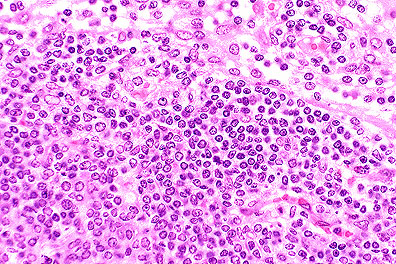

Proliferation of blastic lymphocytes in a male C3H 1pr/1pr mouse. (HE, 400K, 127K)

Contributor's Diagnosis and Comments: Lymphoproliferation disorder. (Looks like lymphoma.)

The 1pr spontaneous mutation in mice is accompanied by generalized lymph node enlargement, hypergammaglobulinemia, anti-DNA antibodies, arthritis and glomerulonephritis resembling systemic lupus erythematosus.

The nodes are greatly enlarged and composed of a monotonous population of medium-sized lymphoid cells with vesicular nuclei and sparse cytoplasm. Mitotic figures are common.

Immunohistochemically, the proliferative cells express B220 strongly (a B cell antigen) and CD3 a T cell antigen (but less so).

AFIP Diagnosis: Lymph node: Atypical lymphoid hyperplasia, diffuse, severe, C3H strain mouse, rodent.

Conference Note: The Fas antigen (Fas) is a cell-surface protein that belongs to the tumor necrosis factor/nerve growth factor receptor family. Fas is known to induce apoptosis and regulate autoreactive T-cells and cytotoxic T lymphocyte mediated cytotoxicity. FAS mRNA is abundantly expressed in the thymus, liver, heart, kidney, and ovary, but is weakly expressed in other tissues. The Fas gene is localized near the 1pr locus on mouse chromosome 19; the gene for its ligand, FasL, is located near the gld region of mouse chromosome 1.

Mice homozygous for 1pr or gld mutations do not initiate apoptosis of lymphocytes. This results in the accumulation of large numbers of nonmalignant T cells in the spleen and lymph nodes.

These mice also suffer from an autoimmune disease similar to systemic lupus erythematosus. As mentioned, Fas plays a significant role in the clonal deletion of autoreactive T-cells. Although the mechanism has not yet been elucidated, it is believed that the loss of this regulation is the cause of the autoimmune disease affecting the mice. It is possible that mutations affecting the Fas gene may cause autoimmune disease in humans.